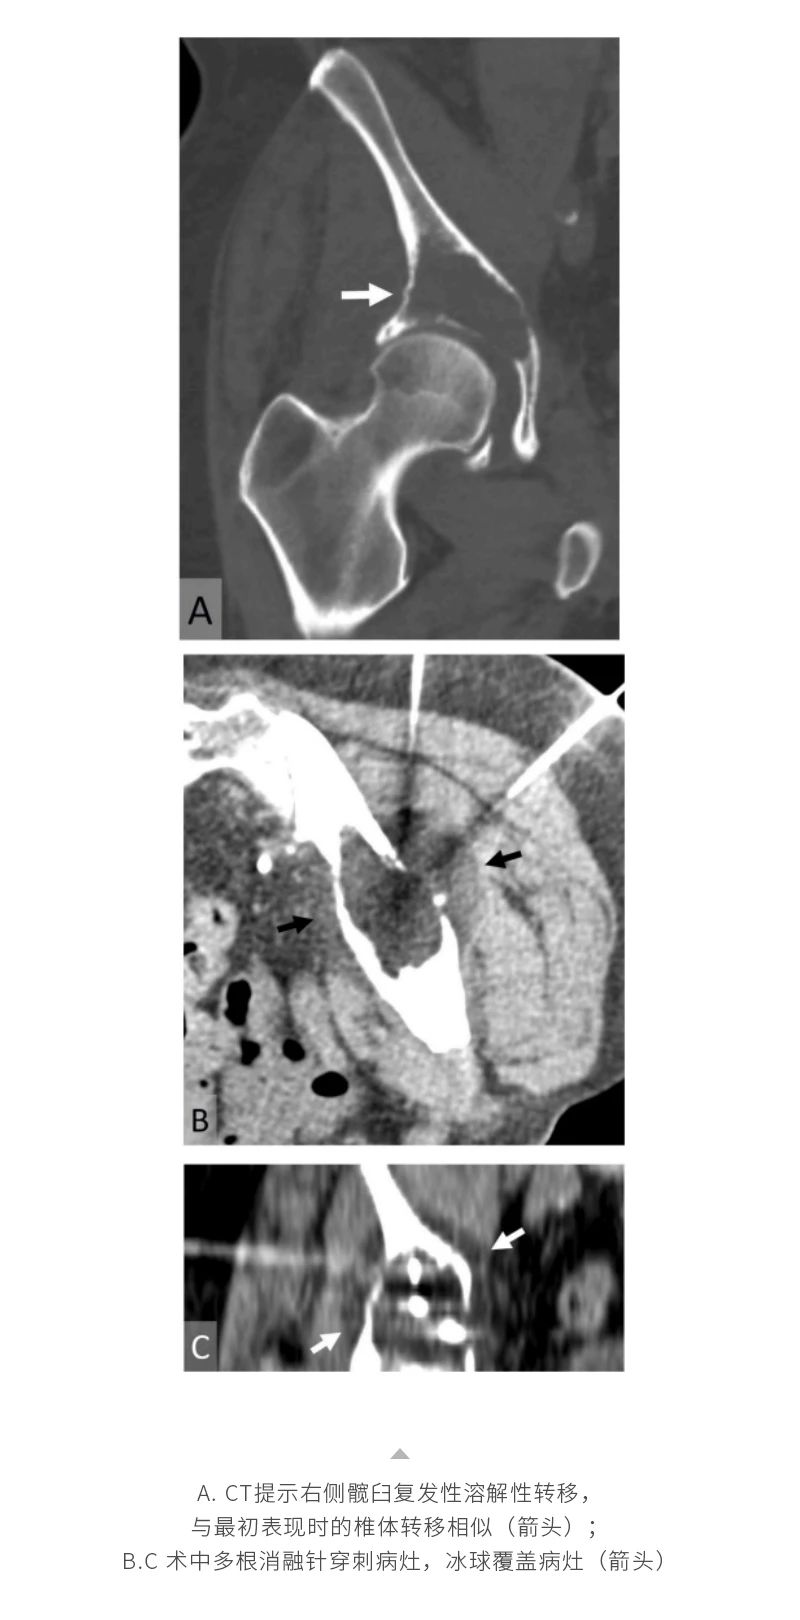

冷凍消融骨腫瘤——【海杰亞科研資訊】第285期

發(fā)布時間:2024-10-18 | 作者:海杰亞 | 瀏覽次數(shù):1108